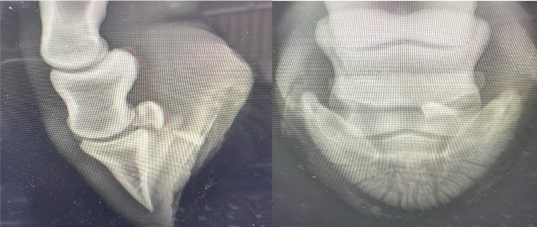

Du modtager to røntgenbilleder fra en kollega, der er blevet kaldt ud til en hest med et indtrådt fremmedlegeme. Din kollega er i tvivl om, hvilken anatomisk struktur, der kan være blevet skadet af fremmedlegemet. Kan du hjælpe?

1 Den elastiske ballepude

2 Hovleddet

3 Den distale seneskede

4 Bursa podotrochlearis

Det rigtige svar er 4